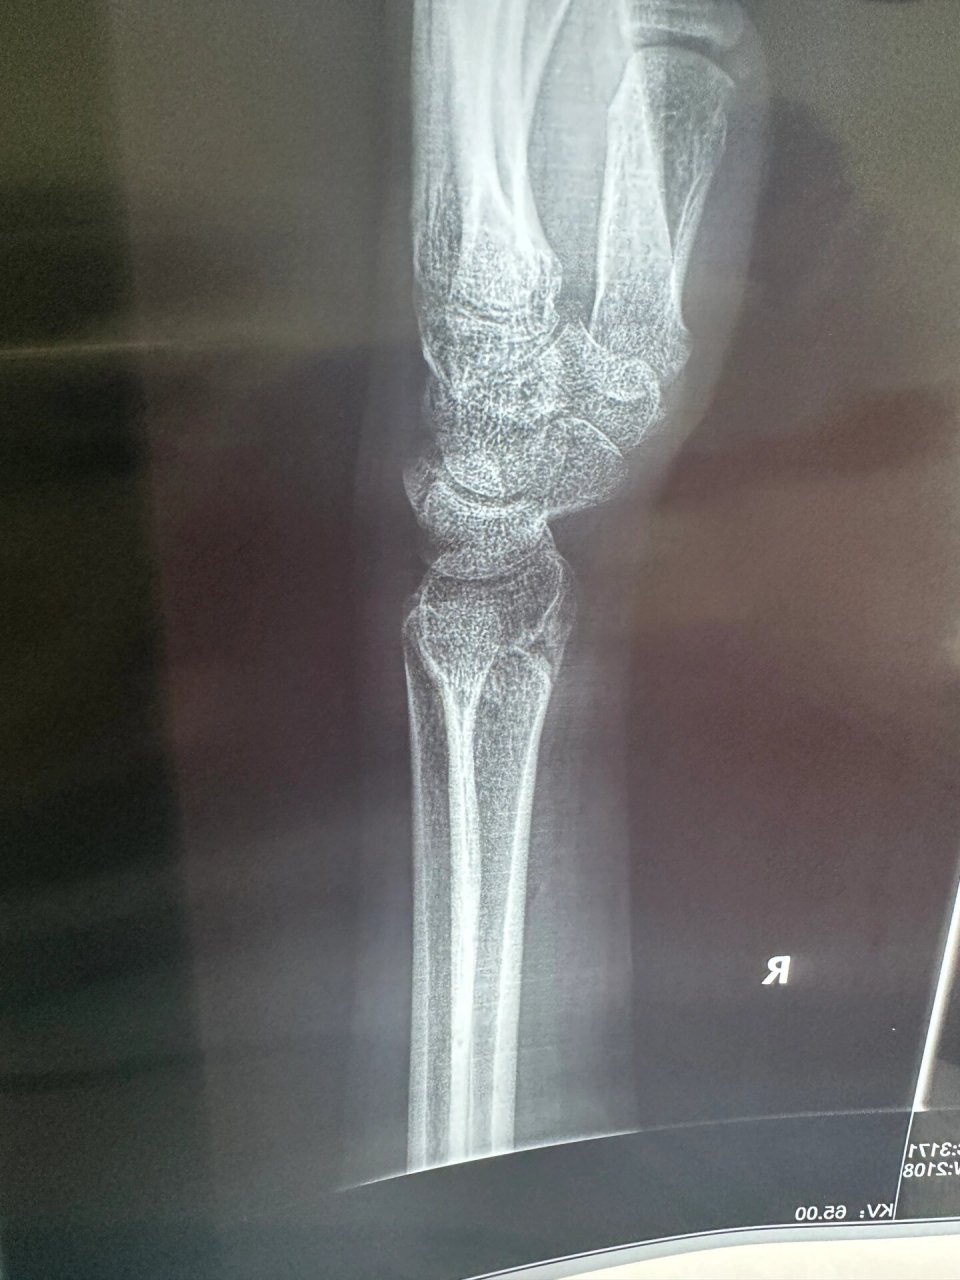

右手桡骨远端骨折,右手尺骨茎突 感觉弯曲的角度大了一点,不知道是不